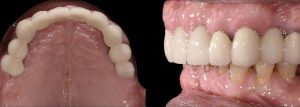

Occlusal and lateral view after periodontal treatment and extraction of tooth 16 and 28. Fig. 2